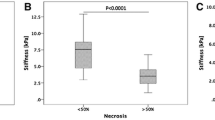

Patients who achieved CR at 6w had significantly lower baseline TS (p = 0.014) and peritumoural LS (p = 0.016) compared to patients classified as PR/SD (Table 2; Fig. 6). Although baseline TS in patients who achieved CR at 6m was lower than in those who did not, the difference was not statistically significant (p = 0.067). There was no significant difference in TS, LS, peritumoural LS, or the change in TS, LS, and peritumoural LS post-RE in patients who achieved OR vs those classified as SD (p > 0.122, Table 2). Baseline serum AFP was significantly lower in patients who achieved OR (p = 0.041) and CR (p = 0.025) at 6w compared to those who did not. There was no significant difference in serum AFP between patients who achieved CR at 6m vs those who did not (p = 0.217). Baseline tumour size was not significantly different in patients who achieved OR at 6w (p = 0.633) and CR at 6w (p = 0.193) or 6m (p = 0.067).

Box plots illustrating the difference in baseline tumour stiffness in patients who achieved OR vs SD (a), patients who achieved CR vs PR and SD (c), and patients in all three response groups (e). Peritumoural liver stiffness in patients who achieved OR vs SD (b), patients who achieved CR vs PR and SD (d), and patients in all three response groups (f) is also shown. CR, complete response; PR, partial response; SD, stable disease; OR, objective response (CR + PR)

The results from ROC analyses are displayed in Table 3. ROC analysis showed that baseline TS and baseline peritumoural LS were both significant predictors of CR at 6w (AUC 0.857, p = 0.015, AUC 0.857, p = 0.017, respectively), although these factors proved not to be significant predictors of OR at 6w or CR at 6m. LS remote from the tumour was not predictive of response at 6w or 6m. Changes in TS and peritumoural/remote LS were not associated with OR at 6w and CR at 6w or 6m (AUC 0.432–0.572, p = 0.232–0.838). Baseline tumour size was not significantly associated with response (AUC 0.577–0.630, p = 0.526–0.710). Baseline serum AFP was a significant predictor of OR (AUC 0.798, p = 0.039) and CR (AUC 0.798, p = 0.025) at 6w but was not a significant predictor of response at 6m. DeLong tests found no significant differences between the diagnostic performance of MRE parameters and AFP in predicting CR at 6w (p = 0.76–0.91). Logistic regression identified no significant combinations of baseline measures of TS/LS, tumour size, or AFP for prediction of OR or CR at 6w or 6m.